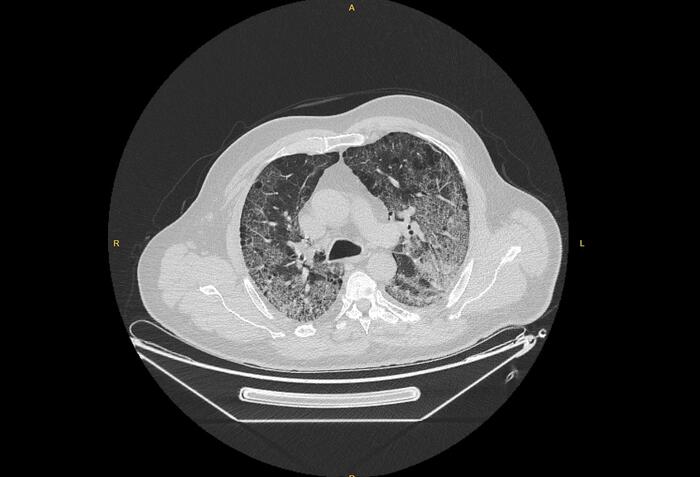

Anadolu Ajansı (AA) Ankara Şehir Hastanesinde Kovid-19 tedavisi gören hastalara ait akciğer görüntülerine ulaştı. Görüntülerde, hastalığın ne kadar hızlı ilerlediği ve akciğerleri nasıl tuttuğu ortaya çıktı.

Prof. Dr. Karalezli, koronavirüsün akciğerleri etkilediği durumda, nefes almanın çok zor olduğunun altını çizerek, halen hastaneye başvuranların da son derece ciddi akciğer tutulumlarının olduğuna vurgu yaptı.

Normalde insanların oksijen seviyelerinin yüzde 98 olduğunu ifade eden Karalezli, koronavirüse yakalananlarda oksijen seviyenin yüzde 70'lere kadar düştüğünü belirtti. Bu durumdaki hastaların oksijen seviyelerini değişik makinalar ve yüksek akım oksijen cihazlarıyla düzeltmeye çalıştıklarını anlatan Karalezli, diğer zatürre durumlarında bu kadar ciddi oksijen düşüklüğü görülmediğine işaret etti.

"İnsanların çok dikkat etmesini istiyoruz. Akciğere girdi mi bunun çıkışı kolay olmuyor. Altta yatan hastalığı varsa biraz ileri yaştaysa çok riskli. Şu an bizim takip ettiğimiz hasta yaş aralığı 40-60 yaş arası. Gençlerde hastalığın seyri çok hızlı gidiyor. Koronavirüs tüm organları tutabiliyor. Akciğer tutulumu varsa tablo kaçınılmaz olarak ilerliyor. İnsanların son derece duyarlı olmasını istiyoruz. Bizler çok yorulduk. Kovid hastalarıyla uğraşıyoruz bakmamız gereken diğer hastalarımız da var. Onlar da sürekli randevu almaya çalışıyorlar."